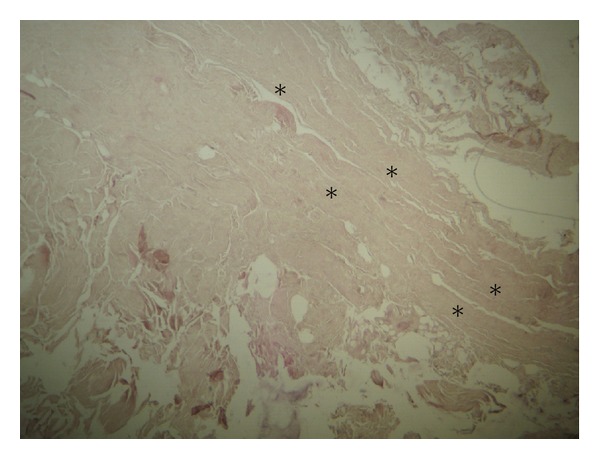

目的。研究了膝关节后外侧角的一种相对未知的韧带结构,即所谓的半月板腓骨韧带(MFL),研究了其宏观形态、组织学特征及其对膝关节运动的反应。材料和方法。在21个新鲜冷冻的未配对膝关节上暴露MFL。显微形态检查利用比较腓骨侧支和腘-腓骨韧带。结果。MFL在100%的标本中表现为在外侧半月板下缘和腓骨头之间延伸的薄条状纤维带。MFL在膝关节伸展和胫骨外旋时呈紧张状态,其组织学特征与腓骨侧支和腘-腓骨韧带相似。讨论。研究了其精确的组织学性质以及膝关节运动时的张力变化。讨论了MFL在避免外侧半月板和外侧冠状韧带撕裂方面的潜在功能意义。结论。在膝关节伸展的最后阶段,MFL可能为外侧半月板以及外侧冠状韧带提供了额外的保护,减少了潜在断裂的可能性。

Purpose. A relatively unknown ligamentous structure of the posterolateral corner of the knee joint, the so-called meniscofibular ligament (MFL), was investigated as regards its macroscopic morphology, its histological features, and its reaction to knee movements. Material and Methods. MFL was exposed on 21 fresh-frozen unpaired knee joints. Its microscopic morphology was examined utilizing for comparison the fibular collateral and the popliteofibular ligament. Results. MFL was encountered in 100% of the specimens as a thin striplike fibrous band extending between the lower border of the lateral meniscus and the head of the fibula. MFL was tense during knee extension and external rotation of the tibia, whereas its histological features were similar to those of fibular collateral and popliteofibular ligament. Discussion. Its precise histological nature is studied as well as its tension alterations during knee movements. The potential functional significance of the MFL with respect to its role in avoidance of lateral meniscus and lateral coronary ligament tears is discussed. Conclusions. MFL presumably provides an additional protection to the lateral meniscus during the last stages of knee extension, as well as to the lateral coronary ligament reducing the possibility of a potential rupture.